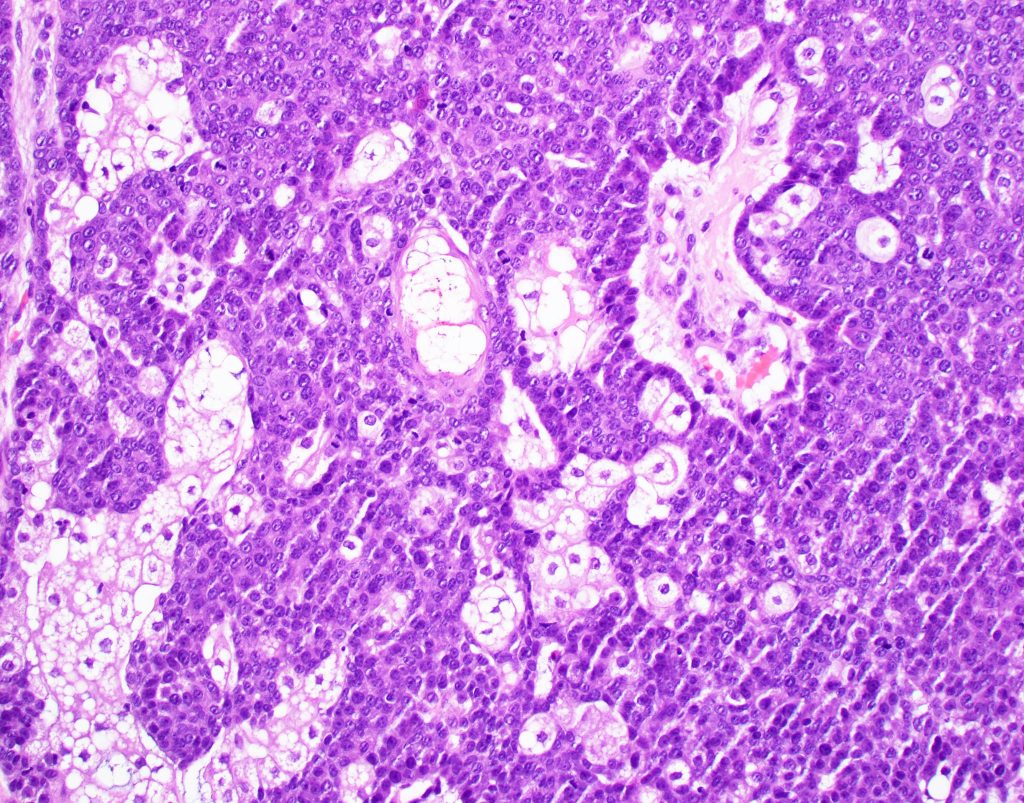

•Random distribution of basaloid cells & sebocytes (<50% sebocytes)

•Duct formation, often with holocrine secretion generally present

•Mitoses sparse to conspicuous

•Absent peripheral palisading & retraction artifact